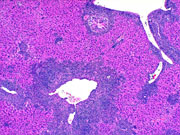

Low magnification of severe myeloproliferative infiltration of the liver. Higher magnification shows dense cellular infiltrates and destruction of hepatocytes. A large number of mature eosinophils are evident.